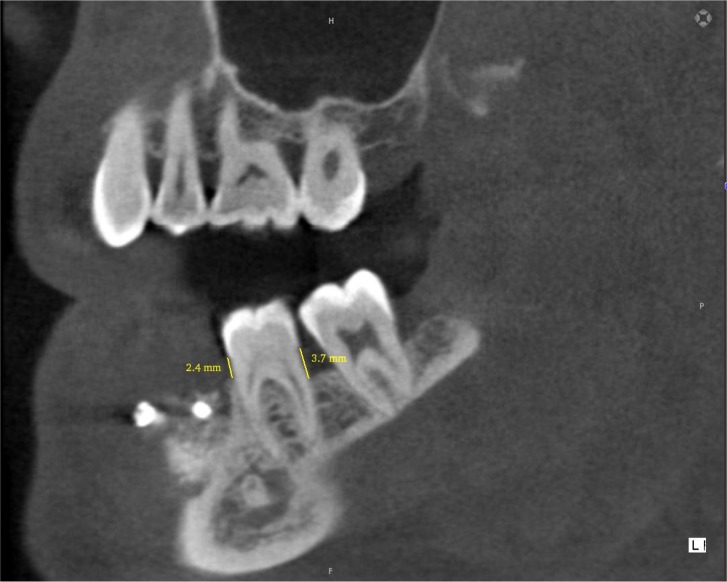

Materials and methods: A study of diagnostic test accuracy was designed and 38 teeth from candidates for dental implant treatment were selected. On CBCT scans, the amount of bone resorption in the buccal, lingual/palatal, mesial and distal surfaces was determined by measuring the distance from the cementoenamel junction to the alveolar crest (normal group: 0-1.5mm, mild bone loss: 1.6-3mm, moderate bone loss: 3.1-4.5mm and severe bone loss: >4.5mm). During the surgical phase, bone loss was measured at the same sites using a periodontal probe. The values were then compared by McNemar's test.

Results: In the buccal, lingual/palatal, mesial and distal surfaces, no significant difference was observed between the values obtained using CBCT and the surgical method. The correlation between CBCT and surgical method was mainly based on the estimation of the degree of bone resorption. CBCT was capable of showing various levels of resorption in all surfaces with high sensitivity, specificity, positive predictive value and negative predictive value compared to the surgical method.